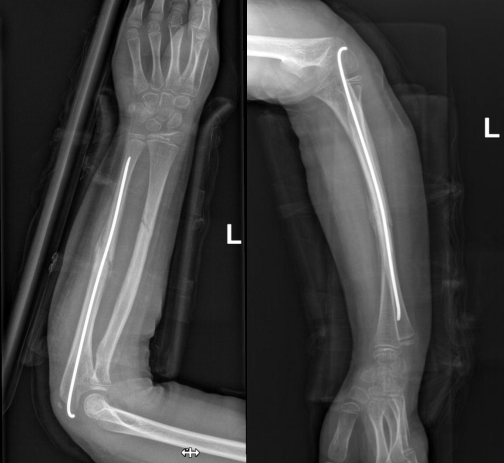

手术过程十分顺利

骨折端对位对线良好

术后伤口仅1厘米

患儿在平稳康复中

术后骨折断端移位好转

力线纠正

手术切口小